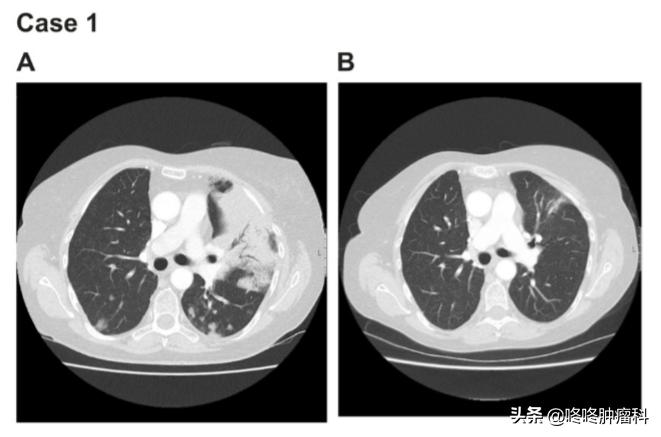

A:2015年2月阿法替尼治疗前评估;B:2015年4月评估

命悬一线之下,患者于2015年2月尝试使用 阿法替尼 (30毫克/天) ,神奇的是,这名患者竟在短短的 2.5个月 使用时间里,迅速达到 部分缓解 (PR) 。且PR时间长达 24个月 。